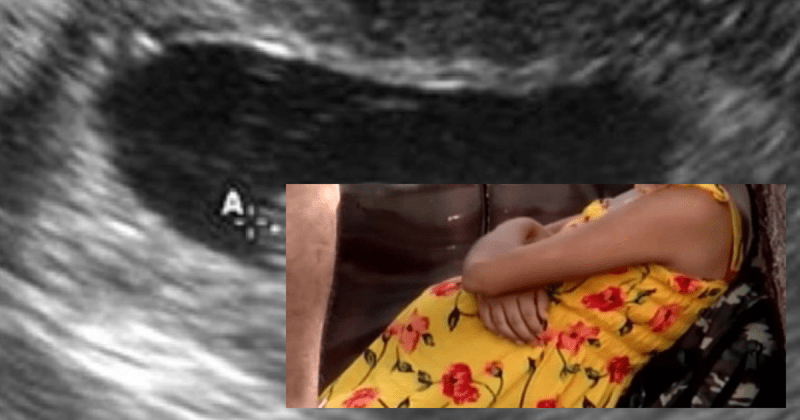

जानकारी के मुताबिक, मंडी के सरकाघाट उपमंडल में 13 साल की मासूम की अचानक तबीयत बिगड़ गई। आनन-फानन में उसके दादा-दादी बच्ची को जोनल हॉस्पिटल लेकर गए। डॉक्टर्स ने जब उसका चेकअप किया और जो सच्चाई बताई उसके बारे में सुनकर सबके होश उड़ गए। डॉक्टर्स ने बताया कि बच्ची गर्भवती है, यह सुनते सबके पसीने छूट गए। फिर उसके घरवालों ने जब इस मामले में लड़की से बात-चीत की तो उसने काफी चौंकाने वाला खुलासा किया। लड़की ने बताया कि इसी साल जनवरी में जब वह स्कूल से घर लौट रही थी, तो पास के रहनेवाले एक युवक ने इसके साथ जबरन रेप किया। उसने बताया कि इस हादसे के बाद वो काफी डर गई और यह सच्चाई किसी को नहीं बताई। उसने कहा कि वो काफी डरी हुई थी, इसलिए इस जिक्र उसने किसी से नहीं किया। लेकिन, चेकअफ के दौरान सारी सच्चाई सामने आ गई और मामले का खुलासा हो गया।